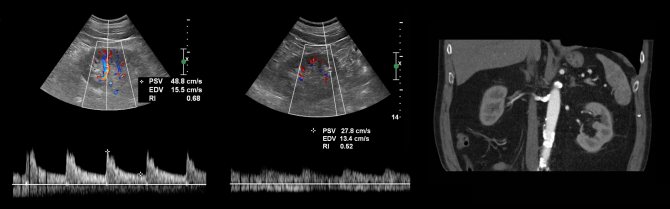

Почечную артерию следует оценивать в семи точках: при выходе из аорты, в проксимальном, среднем и дистальном сегментах, а так же верхушечную, среднюю и нижнюю сегментарные артерии. Оцениваем пиковую систолическую (PSV) и конечно-диастолическую (EDV) скорости кровотока, индекс резистивности (RI), время ускорения (АТ), индекс ускорения (PSV/АТ). Подробнее смотри Доплер сосудов.

Нормальный спектр почечных артерий имеет выраженный систолический пик с антеградным диастолическим потоком на протяжении всего сердечного цикла. У взрослых в норме на главной почечной артерии PSV 100±20 см/сек, EDV — 25-50 см/сек, у детей раннего возраста PSV 40-90 см/сек. В сегментарных артериях PSV падает до 30 см/сек, в междолевых до 25 см/сек, в дуговых до 15 см/сек и междольковых до 10 см/сек. RI в воротах почки <0,8, RI на внутрипочечных артериях 0,34-0,74. У новорожденного RI на внутрипочечных артериях достигает 0,8-0,85, к 1 месяцу опускается до 0,75-0,79, к 1 году до 0,7, у подростков 0,58-0,6. В норме PI 1,2-1,5; S/D 1,8-3.

Рисунок. Нормальный спектр почечных артерий — высокий систолический пик, антеградный диастолический поток, низкое периферическое сопротивление — RI в норме <0,8.